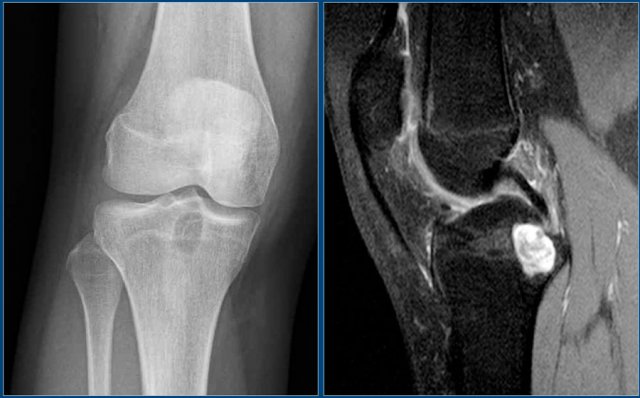

Degenerative cyst versus intraosseus ganglion

Here a well-defined lucent lesion in the epiphysis of the proximal tibia in young patient.

On the sagittal T2WI with FS, the lesion has high SI, but there is no extensive edema, which makes the diagnosis chondroblastoma less likely.

In an older patient with arthrosis the most likely diagnosis would be a degenerative cyst.